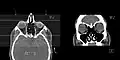

The coronal plane (also known as the frontal plane) is an anatomical plane that divides the body into dorsal and ventral sections. It is perpendicular to the sagittal and transverse planes.

The coronal plane is an example of a longitudinal plane. For a human, the mid-coronal plane would transect a standing body into two halves (front and back, or anterior and posterior) in an imaginary line that cuts through both shoulders. The description of the coronal plane applies to most animals as well as humans even though humans walk upright and the various planes are usually shown in the vertical orientation.